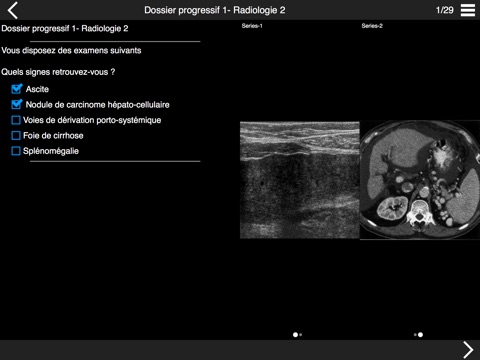

QEVLAR ECNi est une application de quiz sur mobiles et tablettes destinée à la préparation aux Épreuves Classantes Nationales informatisées (ECNi). Elle permet de s’entraîner à répondre à des Dossiers Progressifs et Questions Isolées sur tablettes, comme cela sera le cas pour les ECNi. Cette application est destinée aux étudiants inscrits auprès dorganismes partenaires dIMAIOS. Qevlar ECNi donne accès à des dossiers progressifs ou questions dun organisme partenaire dIMAIOS, ainsi quà des packs de questions des conférences que vous désirez suivre. Votre organisme de formation vous tiendra informé de la disponibilité de nouvelles conférences. Pour les afficher, veuillez actualiser la liste des conférences dans lapplication. Une connexion internet nest pas nécessaire pour répondre au quiz. Il vous faudra par contre une connexion à internet pour télécharger les packs de questions et pour synchroniser les conférences.